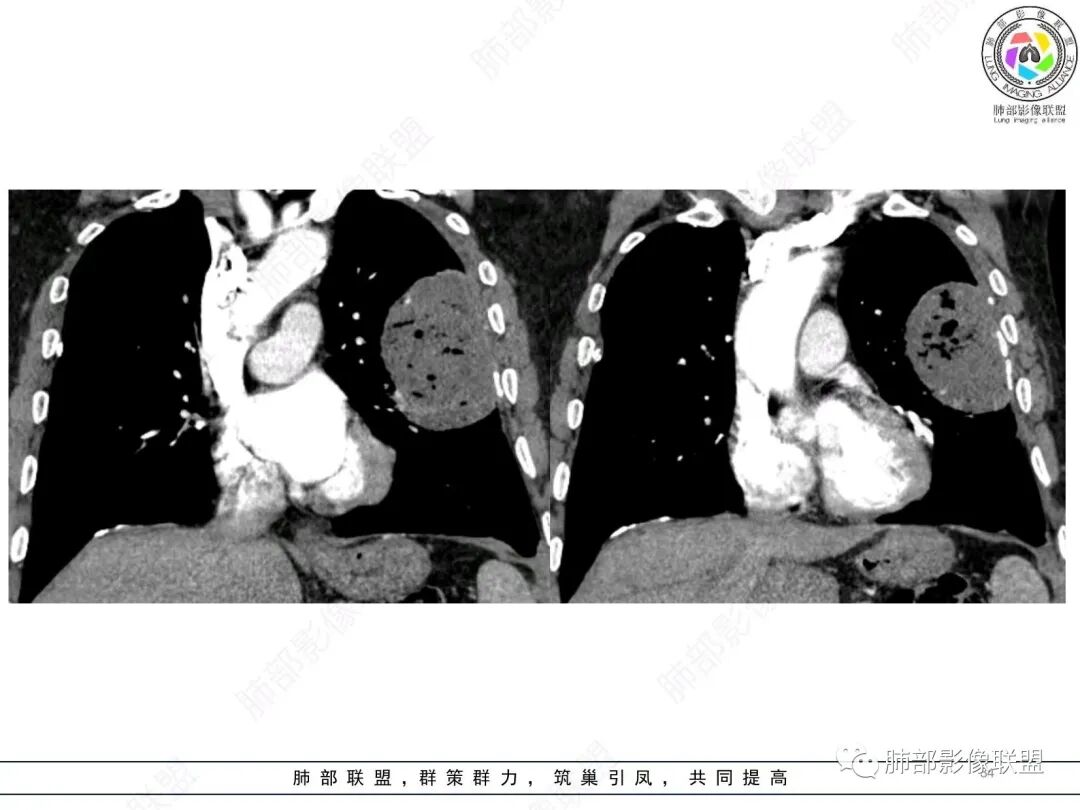

左肺上叶大肿块,膨胀性生长,边界清,密度较低,见部分坏死区,强化弱,肿块见支气管充气V扩张征,分布僵直,枯树枝特点,另一个重要特点血管造影征,淋巴瘤,肿块长轴与胸膜平行,与隐球菌鉴别,隐球荚膜抗原检查,明确诊断经皮肺穿刺。另胸膜钙化(问诊既往有无患胸膜炎病史)。

左肺上叶胸膜下肿块,宽基底与胸膜相连,跨叶裂,边缘清晰膨隆,其内支气管充气,部分扩张、僵直,无明显强化,血管造影征,考虑淋巴瘤,鉴别腺癌

左肺胸膜下巨大占位,跨叶裂,宽基底与胸膜相连,胸膜钙化,平扫密度较低,强化不明显,可见内部血管显影,支气管充气征和扩张,考虑为恶性,倾向于淋巴瘤

左侧胸腔巨大肿块,跨叶生长,临近胸膜钙化,边缘模糊,可见支气管影,定位肺内,增强后轻度强化,边缘见血管影,考虑淋巴瘤,鉴别肉瘤

支持淋巴瘤,左上肺大肿块,有分叶,边缘光整,病灶内密度不均,可见支气管扩张征,增强后可见血管影征。周围肺野清晰。

左肺上叶肿块,宽基底与胸膜相连,跨叶裂,边缘清晰膨隆,可见小分叶,其内支气管充气,部分扩张、僵直,呈枯枝征,支气管达边征,增强无明显强化,可见血管造影征,考虑恶性病变,淋巴瘤,鉴别粘液腺癌。

大肿块,边缘光滑,深分叶

近端支气管堵塞、推移为主

部分类似于脐凹征

内部支气管扩张

肺动脉推移为主,边缘部分进入